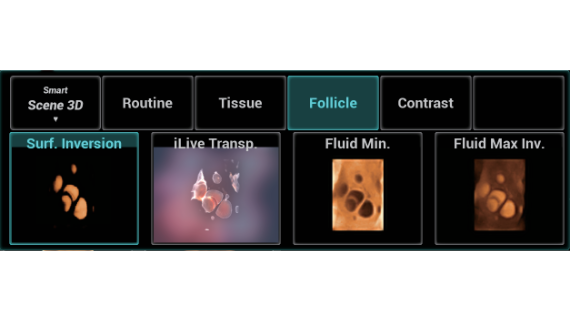

Full-stack Solution Powered by ZST?+

The ZST+ platform is an extraordinary innovation, representing an ultrasound evolution. Transforming ultrasound metrics from conventional beam-forming to channel data based processing. It overcomes the traditional trade-off limitation among spatial resolution, temporal resolution and tissue uniformity, delivering exceptional image quality for infinite imaging solutions with non-stop improvements.